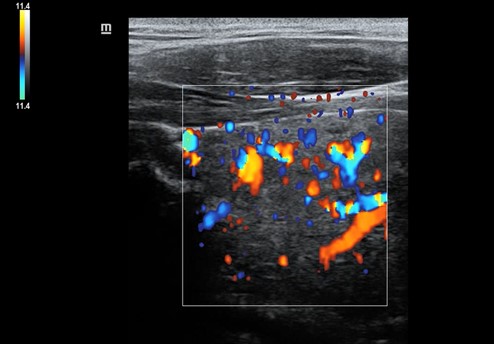

Una vez realizada la anamnesis y la exploración física, se decide realizar una ecografía clínica en la consulta, donde se objetiva un aumento difuso de tamaño del lóbulo tiroideo derecho (33,9 x 38,7 mm), levemente hipoecogénico, con áreas anecoicas en su interior y adenopatías asociadas. Se aplica Doppler color resultando positivo.